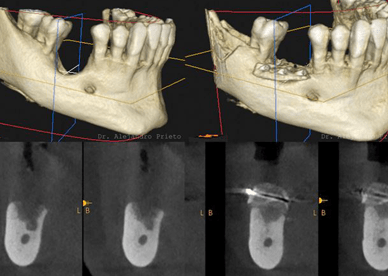

Implantes dentales en Madrid – calidad y precio en Barrio Salamanca En Dr. Alejandro Prieto Dental Clínica Dental, tu clínica dental de confianza en el Barrio Salamanca de Madrid, somos expertos en implantes dentales de todos los tipos. Mezclamos implantología avanzada con alta estética. Si estás buscando una solución duradera, estética y con precios competitivos, […]